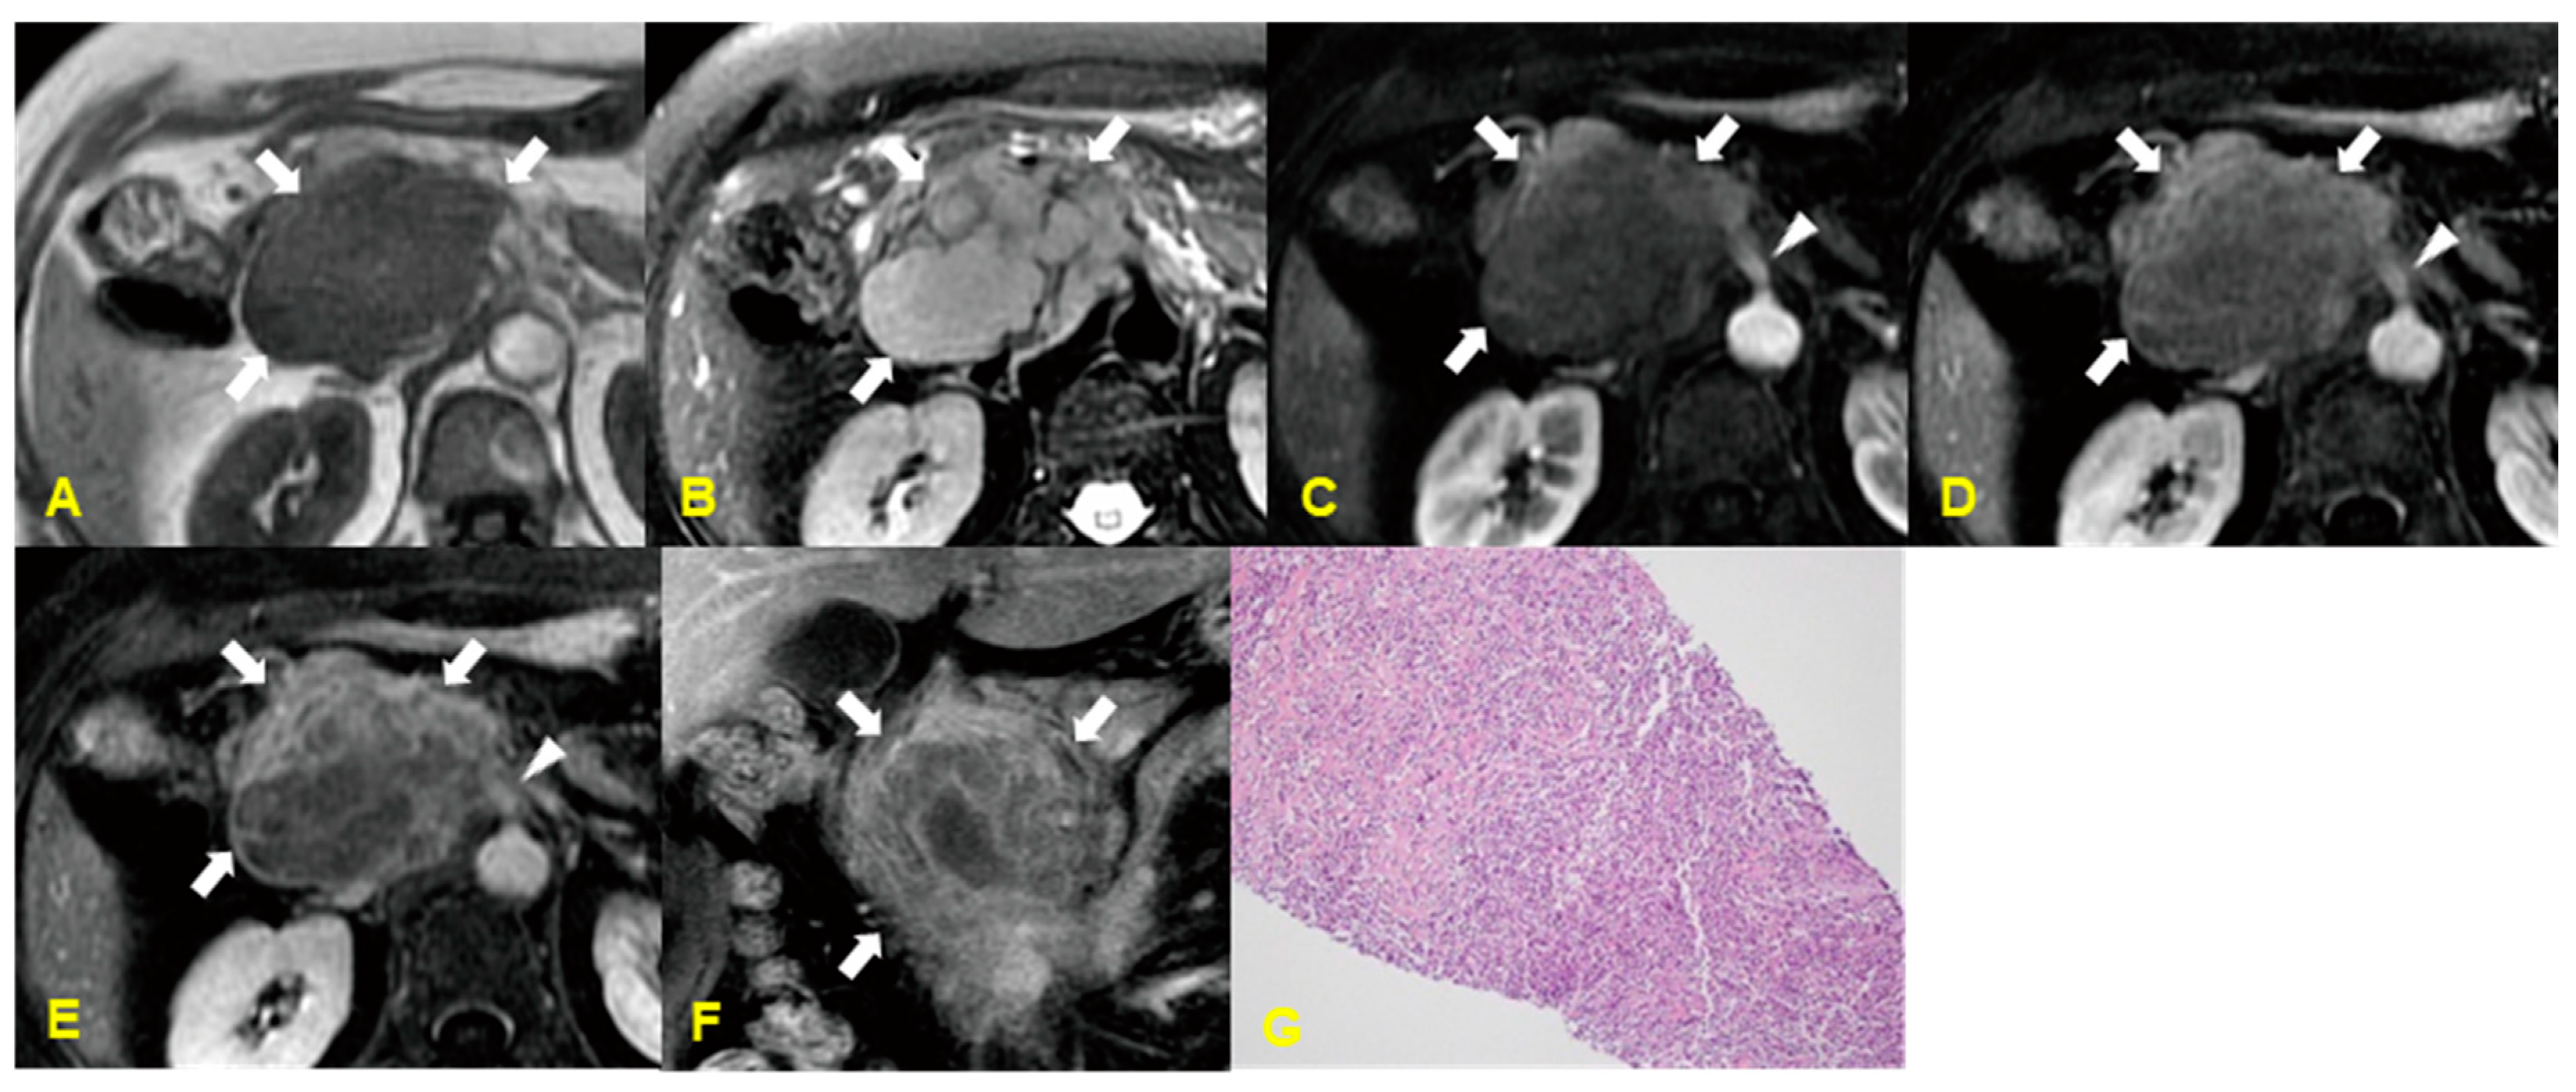

6. Primary Pancreatic Lymphoma (PPL)

6.1. Imaging Finding

6.2. Differential Diagnosis

| Primary lymphoma | Localized type: well defined mass with poor enhancement/Low-to-intermediate SI on T2WI |

| Diffuse infiltrating type: hypointense enlarged pancreas on T1- and T2WI | |